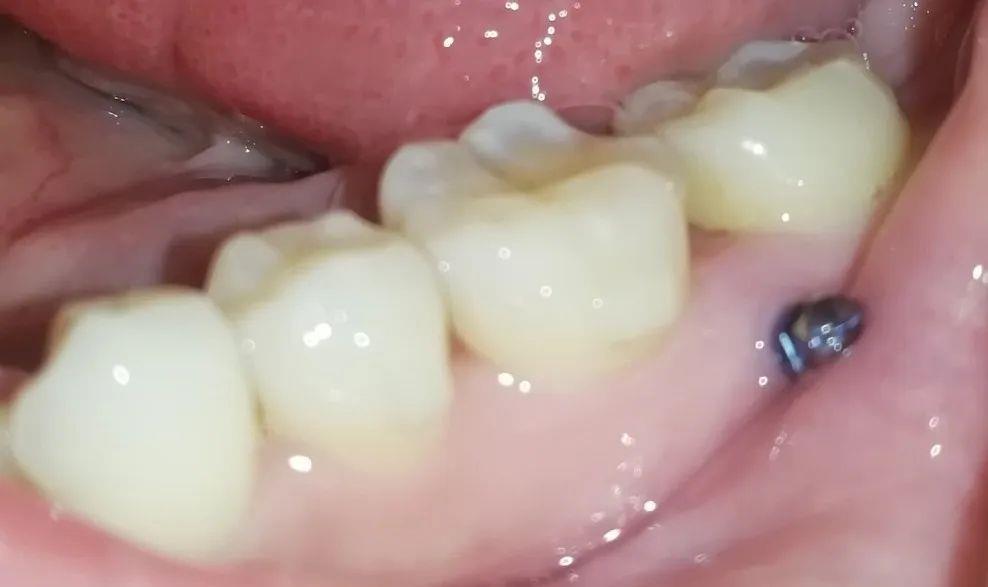

可以大致看看牙钉的位置